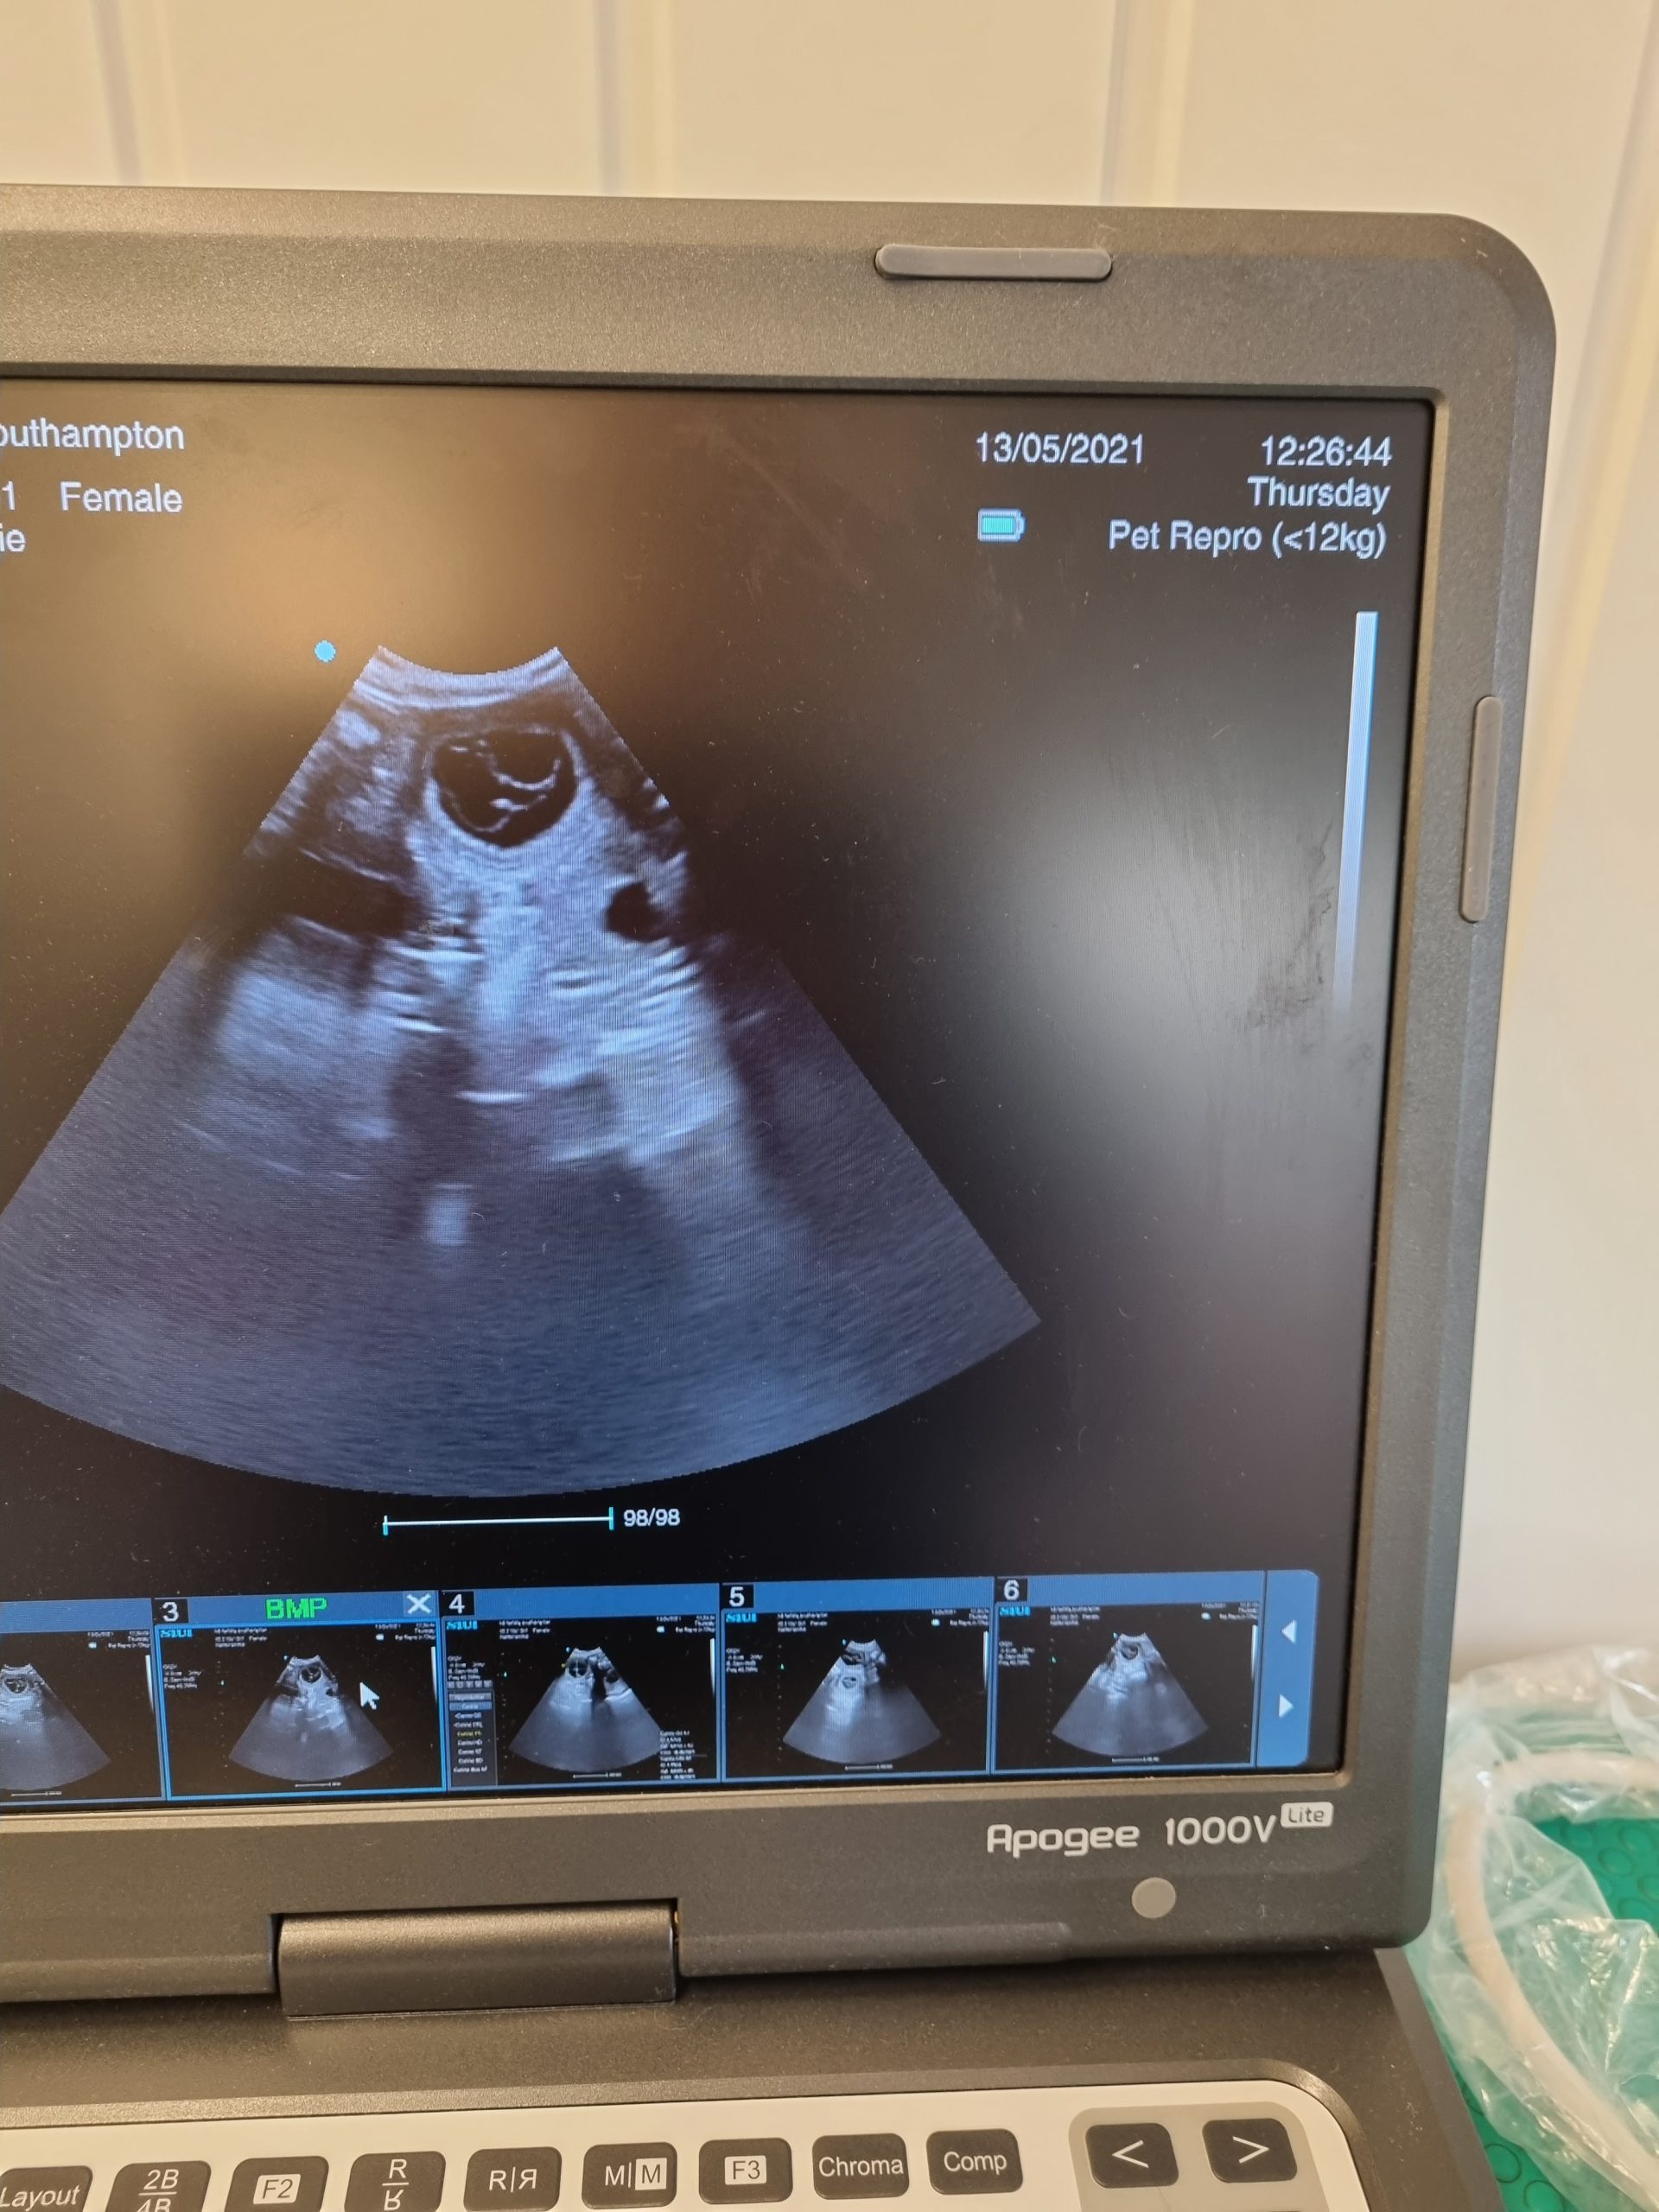

This 5 week pregnancy scan identified at least four puppies, all healthy, moving around and with strong heartbeats.